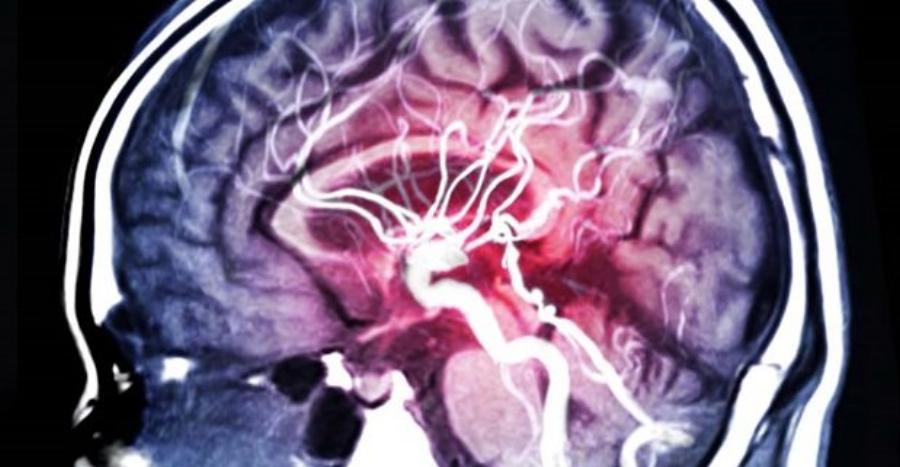

Τραγική είναι η είδηση με μια νεαρή γυναίκα η οποία είχε έντονο πονοκέφαλο και νόμιζε πως είχε ημικρανία, όμως δυστυχώς η κατάσταση της υγείας της ήταν πολύ σοβαρή καθώς έφυγε από την ζωή από ανεύρυσμα στον εγκέφαλο.

Από ανεύρυσμα εγκεφάλου πέθανε μία 30χρονη γυναίκα, που νόμιζε ότι είχε ημικρανία, επί δύο συνεχείς εβδομάδες. Συγκεκριμένα, η 30χρονη για δύο εβδομάδες είχε πολύ έντονους πονοκεφάλους και νόμιζε ότι ήταν όπως όλες τις άλλες φορές, που ταλαιπωρούνταν από τις ημικρανίες της. Έπαιρνε πολλά παυσίπονα, αλλά αυτή την φορά δεν βοηθούσαν, καθώς ο πόνος συνέχιζε να είναι δυνατός και επίμονος. Μάλιστα, κάποια στιγμή κατάλαβε ότι δεν βλέπει καλά από το ένα μάτι, έβλεπε την τηλεόραση μισή και νόμιζε ότι οφείλεται και αυτό στον δυνατό πονοκέφαλο.

Ήρθε όμως η στιγμή που κατάλαβε ότι τελικά ο πόνος δεν ήταν συνηθισμένος, αφού ξύπνησε και δεν μπορούσε να κουνήσει ούτε χέρια ούτε πόδια, το στόμα της είχε στραβώσει και το μόνο που μπορούσε να κάνει ήταν να βγάζει κάποιες κραυγές. Το ασθενοφόρο που την παρέλαβε έκανε όσο πιο γρήγορα γινόταν την διαδρομή μέχρι το νοσοκομείο, ωστόσο, ήταν πολύ αργά, καθώς άφησε την τελευταία της πνοή και ήταν μόλις 30 χρονών.

Ένας έντονος πονοκέφαλος μπορεί να είναι ημικρανία, αλλά μπορεί να αποτελεί και ένδειξη για κάτι πολύ πιο σοβαρό, οπότε εάν ο πόνος δεν περνάει, δεν θα πρέπει να τον αγνοούμε ή να προσπαθούμε να τον αντιμετωπίσουμε με παυσίπονα, αλλά να απευθυνθούμε άμεσα σε ειδικό. Το ανεύρυσμα εγκεφάλου μοιάζει με ένα μικρό μπαλόνι που μπορεί να «σκάσει» οποιαδήποτε στιγμή και η ρήξη του ανευρύσματος αποτελεί επείγουσα κατάσταση. Εάν το ανεύρυσμα έχει σχηματιστεί σε αιμοφόρο αγγείο του εγκεφάλου, η ρήξη συνεπάγεται ότι διαρρέει αίμα στους γύρω ιστούς. Το ανεύρυσμα δεν γίνεται αντιληπτό εκτός κι αν επέλθει η ρήξη. Εκτιμάται ότι ποσοστό 6-9% του πληθυσμού έχει ανεύρυσμα χωρίς να το γνωρίζει.

Η ρήξη βέβαια δεν συμβαίνει πάντα. Μάλιστα, ακόμη κι αν το ανεύρυσμα εντοπιστεί έγκαιρα, για παράδειγμα κατά τη διάρκεια εξέτασης (π.χ. μαγνητική ή άλλη απεικονιστική εξέταση), οι γιατροί δεν συνιστούν κάποια θεραπευτική παρέμβαση εκτός κι αν το μέγεθός του είναι αρκετά μεγάλο ή αν ο ασθενής έχει οικογενειακό ιστορικό ρήξης ανευρύσματος. Το ανεύρυσμα είναι ένα παθολογικό «φούσκωμα» σε μία από τις μεγάλες αρτηρίες του εγκεφάλου. Το «φούσκωμα» αυτό έχει σαθρά τοιχώματα, και κάποια στιγμή μπορεί να σπάσει. Λίγες φορές τα ανευρύσματα του εγκεφάλου οφείλονται σε λοιμώξεις, σύνδρομα ή άλλα αίτια. Στην μεγάλη πλειοψηφία των περιπτώσεων («σακκοειδή» ανευρύσματα) δεν υπάρχει εμφανής προηγούμενη νόσος υπεύθυνη για την δημιουργία του ανευρύσματος.

Πιθανολογείται πως σε κάποιους ανθρώπους υπάρχουν μικροανωμαλίες εκ γενετής στο τοίχωμα αρτηριών του εγκεφάλου, που με τα χρόνια οδηγούν στην δημιουργία ανευρύσματος. Παράγοντες που μπορεί να έχουν συμβολή στη δημιουργία αυτή είναι οι γνωστοί αγγειολογικοί παράγοντες κινδύνου (αρτηριακή υπέρταση, υπερχοληστεριναιμία, κάπνισμα κλπ). Από την στιγμή που ένα ανεύρυσμα εγκεφάλου δημιουργείται, συνήθως μεγαλώνει σταδιακά σε μέγεθος και επίσης μεγαλώνει (αθροιστικά) ο κίνδυνος να σπάσει: π.χ. αν ο κίνδυνος αιμορραγίας είναι 1% ανά έτος, τότε αθροιστικά είναι 10% στην δεκαετία. Συνηθέστατα το ανεύρυσμα δεν προειδοποιεί πριν σπάσει.

Σπανιότερα, μπορεί να υπάρχουν πρόδρομα συμπτώματα που μπορεί να οφείλονται σε «προειδοποιητικές» μικροαιμορραγίες (ασυνήθιστοι πονοκέφαλοι μαζί με εμετό) ή σε πίεση νευρικού ιστού από το ανεύρυσμα (π.χ. διπλωπία ή άλλα ασυνήθιστα νευρολογικά συμπτώματα). Η κλινική εικόνα της ρήξης του ανευρύσματος συνήθως είναι αιφνίδια και δραματική, γι’ αυτό έχει χαρακτηριστεί «κεραυνός εν αιθρία». Εάν η ρήξη του ανευρύσματος συμβεί αιφνιδίως, διαρρέει αίμα για μερικά δευτερόλεπτα έως ότου τα αιμοπετάλια σχηματίσουν στο σημείο αιματόπηγμα (θρόμβο). Σε ορισμένους ασθενείς, μερικές ημέρες ή εβδομάδες πριν τη ρήξη παρατηρούνται μικρές «διαρροές» αίματος από το σημείο του ανευρύσματος. Το αίμα που διαρρέει αυξάνει την πίεση εντός του κρανίου και διαταράσσει τη φυσιολογική ροή αίματος προς τον εγκέφαλο. Ο ασθενής απροειδοποίητα «κεραυνοβολείται» από μια πολύ ισχυρή κεφαλαλγία (πονοκέφαλο) που συνήθως εντοπίζεται στο πίσω μέρος του κεφαλιού και στον αυχένα. Πολλές φορές ο πονοκέφαλος αυτός είναι τόσο ισχυρός και απότομος που αναγκάζει τον πάσχοντα να πέσει κάτω ή να γονατίσει.

Νεκρή 30χρονη από ανεύρυσμα: Ποια είναι τα συμπτώματα

Ο ασθενής αισθάνεται σαν «κάποιος να ήρθε από πίσω και να κτύπησε το κεφάλι με σφυρί». Σχεδόν πάντα ο ασθενής κάνει και εμετό. Από κει και πέρα : στις βαρύτερες περιπτώσεις, ποσοστό περίπου 50%, ο ασθενής πεθαίνει επί τόπου πριν προλάβει να φτάσει στο νοσοκομείο. Η εγκεφαλική αιμορραγία είναι μια από τις συχνότερες αιτίες αιφνίδιου θανάτου, δεύτερη μετά τα καρδιαγγειακά επεισόδια. Η αντιμετώπιση του υπόλοιπου 50% των ασθενών, αυτών δηλαδή που φτάνουν ζωντανοί στο νοσοκομείο, πρέπει να είναι γρήγορη και εξειδικευμένη. Προέχει η θεραπεία του ανευρύσματος για να μην ξανασπάσει, αφού σε ασθενείς που έχουν ήδη αιμορραγήσει ο κίνδυνος δεύτερης αιμορραγίας είναι σοβαρότατος. – Η διάγνωση της κατάστασης μπορεί να γίνει άμεσα με επείγουσα αξονική τομογραφία (CT) εγκεφάλου που δείχνει την αιμορραγία, και μπορεί επί τόπου να συμπληρώνεται με αξονική αγγειογραφία που θα δείξει και το ανεύρυσμα εγκεφάλου. Συνήθως ακολουθεί και ψηφιακή αγγειογραφία εγκεφάλου (DSA).

Η θεραπεία του ανευρύσματος για να μην ξανααιμορραγήσει σήμερα συνήθως γίνεται με ειδική ενδαγγειακή τεχνική (μέσα από τα αγγεία με «εμβολισμό», χωρίς ανοικτή επέμβαση). Σε περιπτώσεις που αυτό δεν είναι εφικτό τεχνικά, η θεραπεία γίνεται με κρανιοτομία και μικροχειρουργική επέμβαση. – Η εντατική θεραπεία σε ειδική μονάδα είναι πολύ σημαντική αφού υπάρχουν σοβαρές επιπλοκές όπως ο «αγγειόσπασμος» (μεθαιμορραγική ισχαιμία) που οφείλονται στην αρχική αιμορραγία και μπορεί να επισυμβούν ακόμα και αν έχει θεραπευτεί το ανεύρυσμα επιτυχώς και έγκαιρα. Όπως είναι προφανές από τα παραπάνω, το ανεύρυσμα εγκεφάλου θυμίζει «ρώσικη ρουλέτα», γι’ αυτό φυσικά το ιδανικό είναι να γίνει η διάγνωση πριν το ανεύρυσμα αιμορραγήσει τότε που συνήθως δεν έχει δώσει συμπτώματα. Έτσι μπορεί να θεραπευτεί πριν σπάσει. Γι’ αυτό οι νευροχειρουργοί εδώ και χρόνια προτείνουν να γίνεται προληπτικός έλεγχος με μαγνητική αγγειογραφία (ΜRA) εγκεφάλου σε όλον τον πληθυσμό.